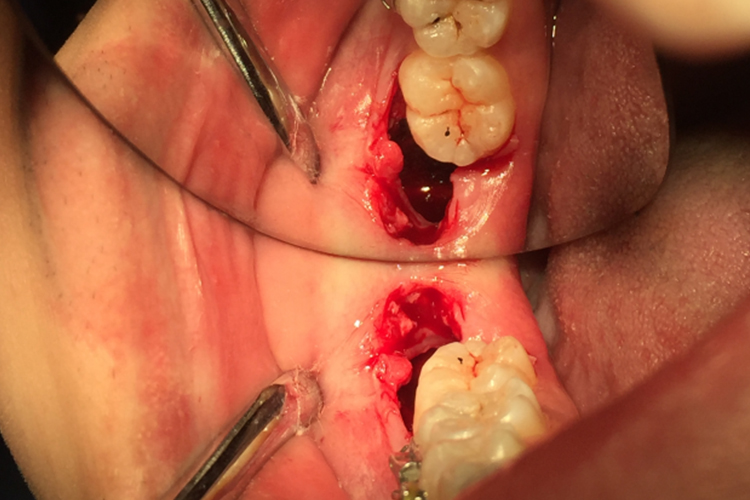

拔完智齿后正常的伤口有一定深度,像个洞,大小与智齿本身相关。术后伤口会立即被血液充满,里面没有碎骨片、碎牙片,后续可形成血凝块,2小时后基本可完全凝结,此时牙龈组织会逐渐收缩,使伤口逐渐变小,周围组织无红肿、化脓等炎症反应。